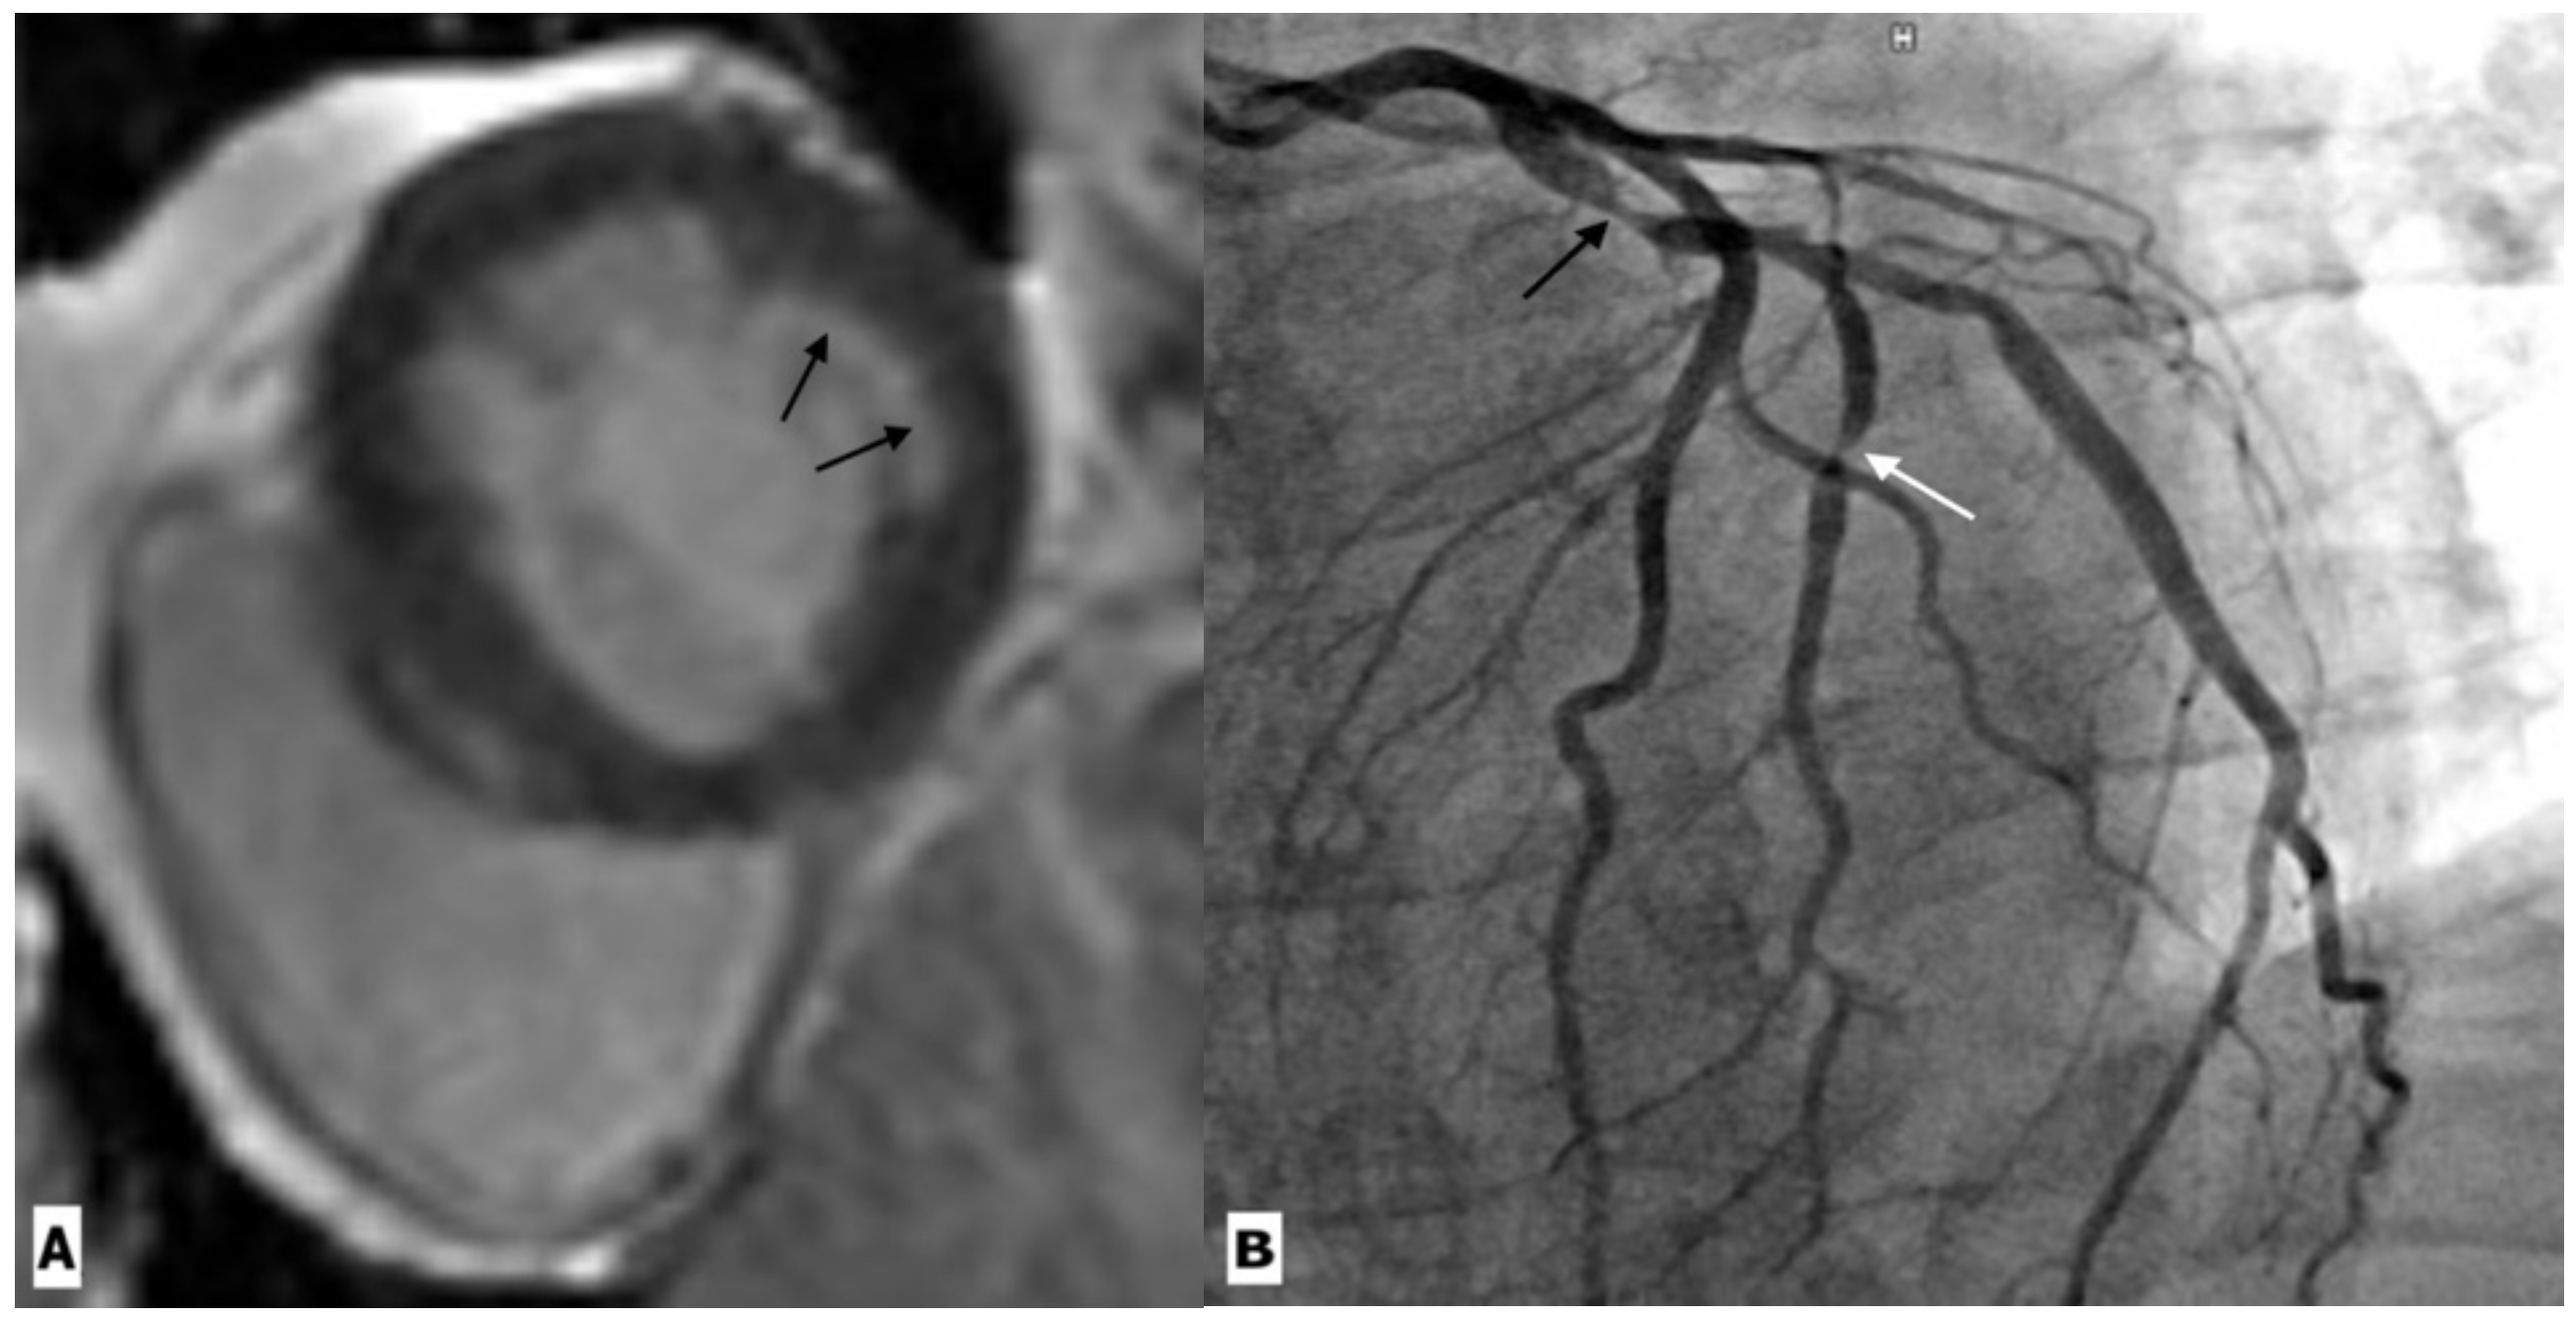

Figure 4.

Cardiac magnetic resonance imaging in a 59-year-old HIV-infected male patient with coronary artery disease. (A) Basal ventricular short-axis view gadolinium enhancement image showing subendocardial enhancement in the inferolateral segment (black arrow). (B) Coronary angiography revealed severe stenosis in the proximal left circumflex artery (black arrow) and its first obtuse marginal branch (white arrow).